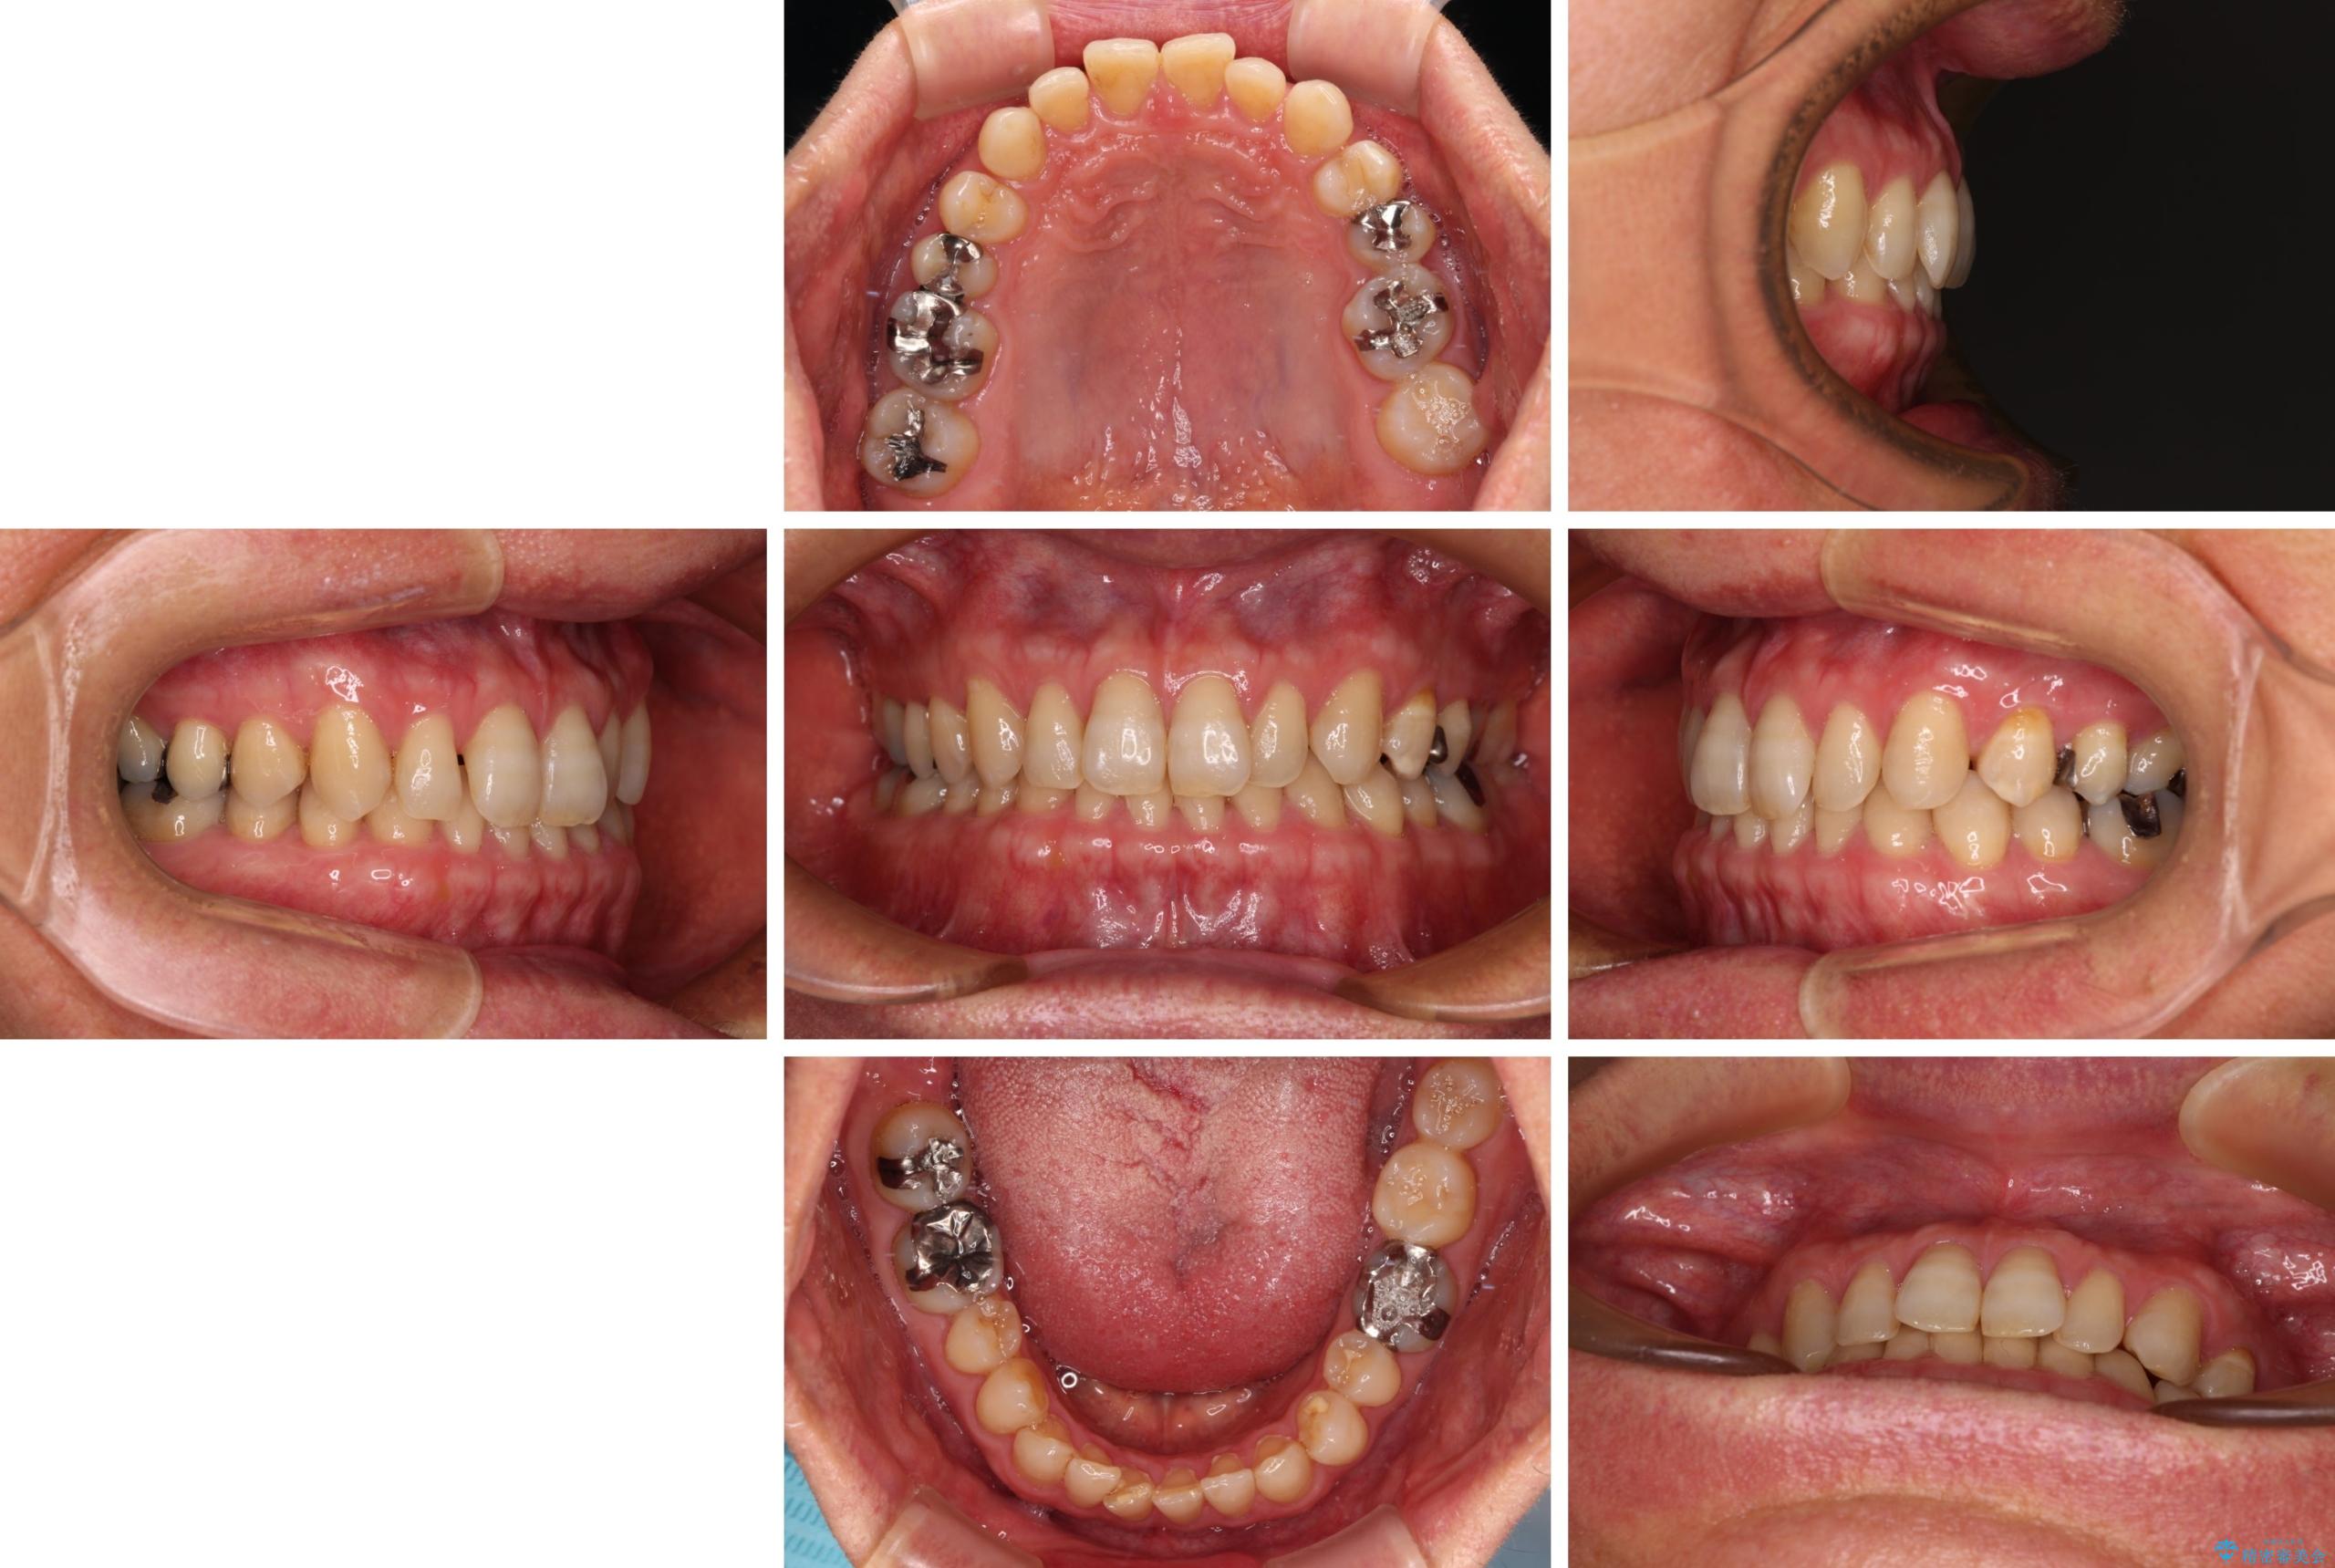

【モニター】ディープバイトで隙間の空いた歯列 ワイヤー装置での非抜歯矯正

- 前歯のデコボコと隙間の空いた歯列を気にして来院された患者様です。

下顎前歯が隠れるほどのディープバイトにより、強い咬合力と突き上げで上顎歯列に隙間が空いている状態でした。

手前に傾斜している奥歯をワイヤー装置で立ち上がらせ、咬み合わせの高さを挙上することで突き上げを解消し、空隙歯列を改善していくこととしました。

ディープバイトが改善され、睡眠時の食いしばりも緩和され、顎への負担が軽減されました。